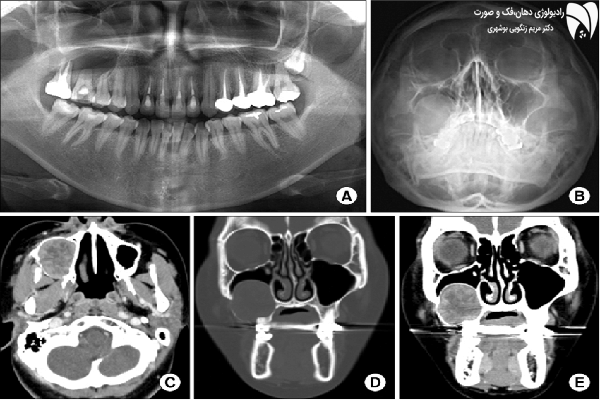

فتوگرافی ارتودنسی شامل عکس هایی از زاویه های مختلف چهره و دندانهاست که باید بسیار دقیق و با کیفیت واز زاویای استاندارد تهیه شود . فتوگرافی ارتودنسی اسکن دقیقی از وضعیت و پارامترهای چهره ، طرح لبخند و دندان های شما به دندانپزشک می دهد و به او کمک می کند تا برای شما بهترین طرح درمان متناسب با پارامترهای صورت طراحی کند و همین طور فرایند پیشرفت درمان را کنترل نماید. با توجه به اهمیت فتوگرافی دندان، بیماران باید در انتخاب بهترین رادیولوژی دهان، فک و صورت دقت بیشتری داشته باشند.

گاهی اوقات در معاینه اولیه دندانپرشک متوجه نقایص و مشکلات بیمار خود نمی شود . فتوگرافی دندان پزشکی و ارتودنسی کمک می کند تا دندانپزشک به دید کلی از وضعیت دندان های شما دست یابد و طرح درمان مناسب ارتودنسی ، ونیرکامپوزیت ، لمینت دندان یا ایمپلنت تجویز کند .عکس پزشکی باید به گونه ای استاندارد انجام شده باشد که پزشک بتواند با استناد به آن طرح درمان دقیقی را طرح ریزی کند .

یکی از مشکلاتی که اغلب دندانپزشک ها با آن دست و پنجه نرم می کنند عدم توجیه بیمار از روند فرایند درمانی خود است . با فتوگرافی می توان مشکل را حل کرد و بیمار را تا حد زیادی از کیفیت درمان خود آگاه کرد .با فتوگرافی می توان نتایج را آنالیز کرد و آن را با وضعیت فعلی بیمار مقایسه کرد تا پزشک و بیمار بتوانند به یک طرح درمان مشترک و قابل پذیرش برسند .